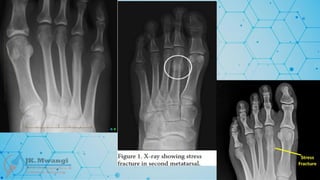

Stress / fatigue fractures

 Normal bone – repetitive (heavy) loading, military personnel

 Common sites?

• Metatarsals, shaft of tibia, shaft of fibula, & NOF